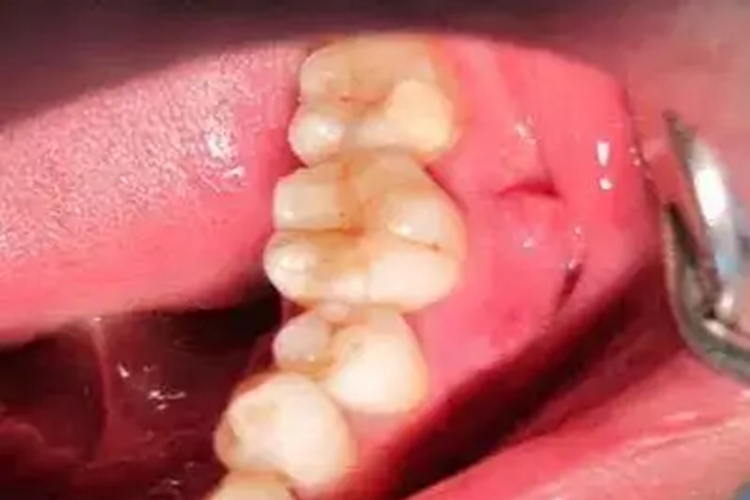

早期牙隐裂以上颌第一磨牙最常见,起先表浅时常无明显症状,较深时则遇冷、热刺激敏感,或有咬合不适感,随着隐裂发展会出现在咬到牙齿的某个特殊部位时会产生酸痛。早期牙隐裂发生的位置多发生在磨牙和前磨牙面,出现细微微裂纹与窝沟重叠。在牙齿叩诊时会出现不适,侧向叩诊反应明显。